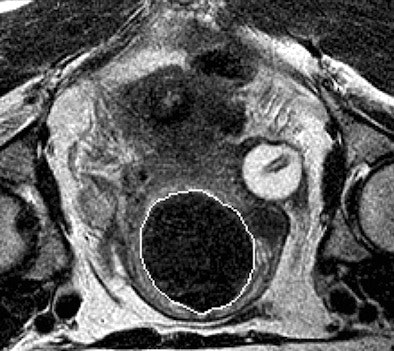

| Above, T2-weighted axial MR image of a hypointense fibroid in a 42-year-old patient before MR-guided focused ultrasound surgery. Below, T1-weighted gadolinium-enhanced axial MR image of the same fibroid immediately after treatment. The outlines of treated fibroid and NPV were contoured with electronic calipers to compute the area per section by using volumetric analysis software. |